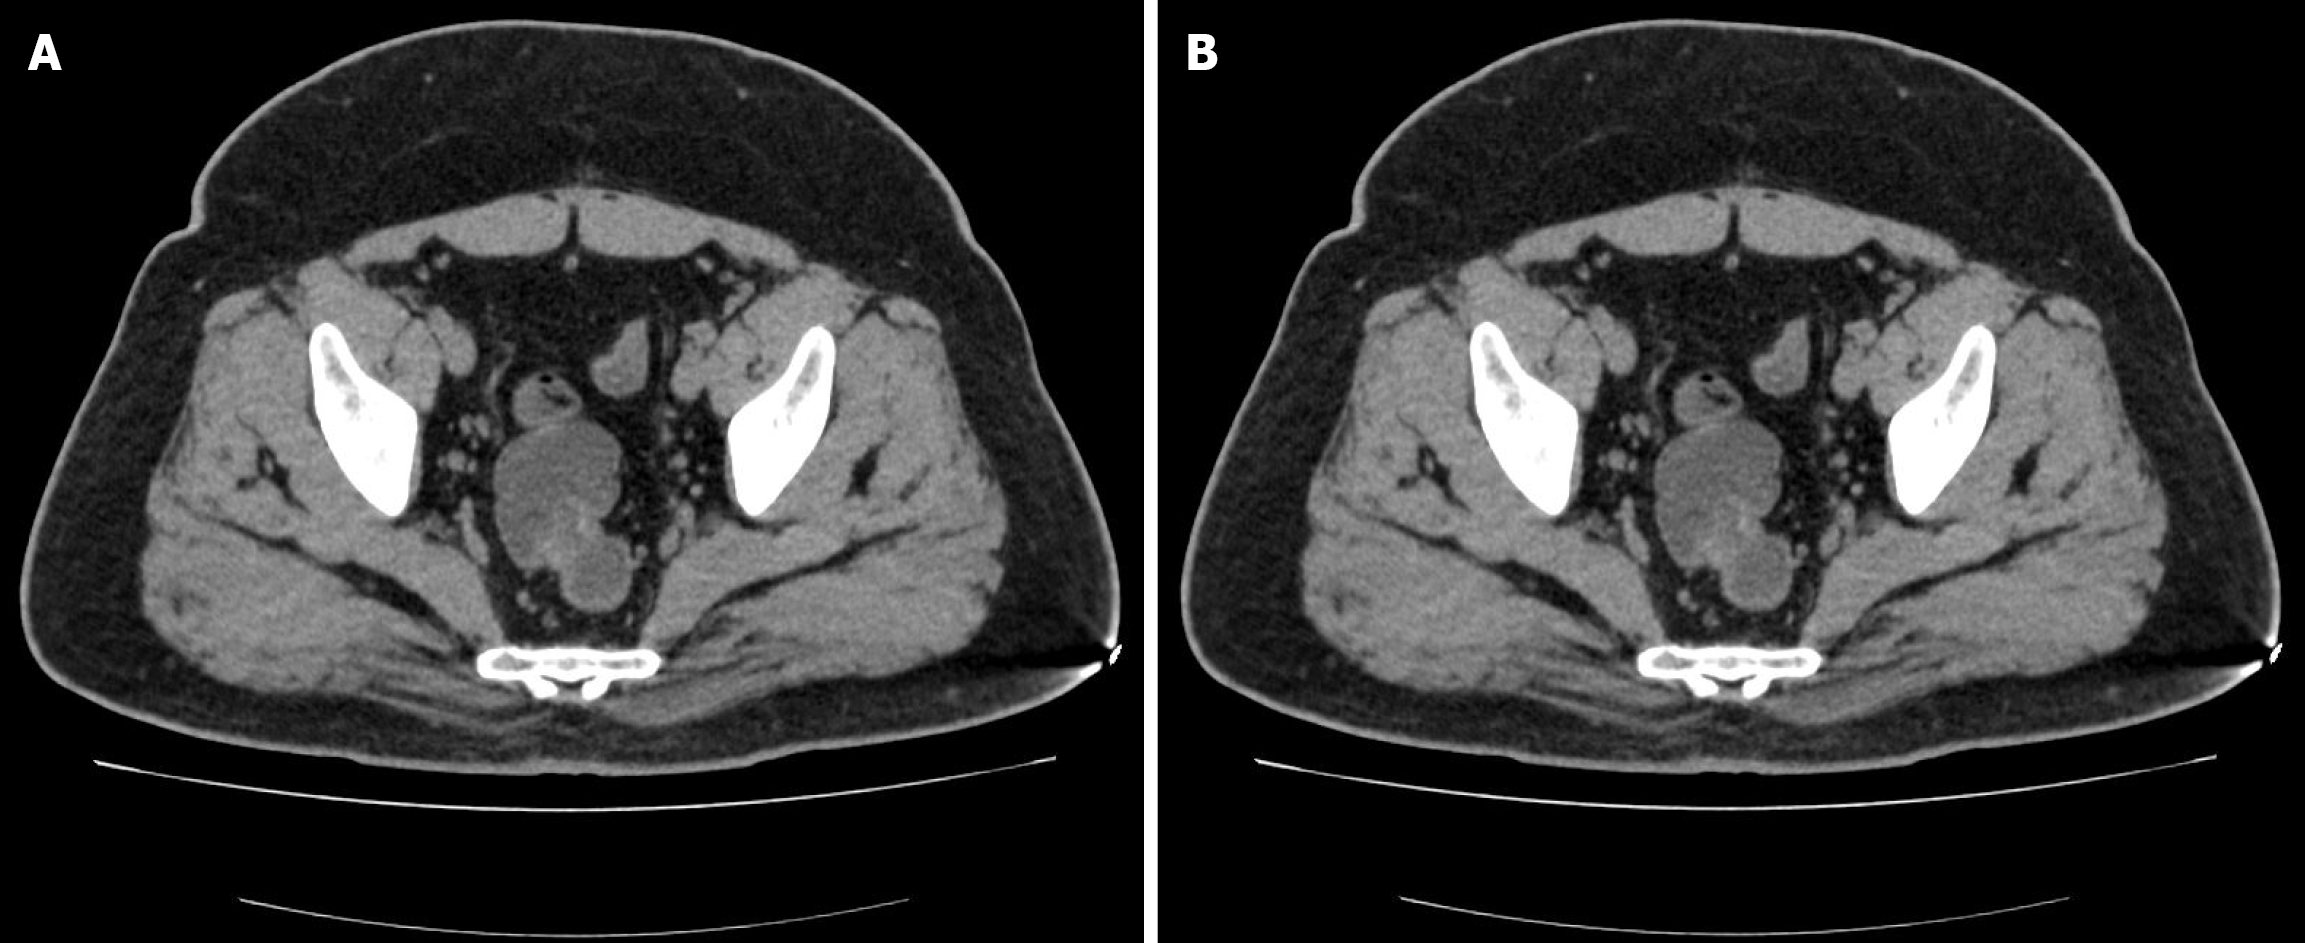

Colonoscopy revealed two large submucosal mass 20 cm and 18 cm from the anal verge (Figure 1). Endorectal ultrasound revealed two cystic mass was observed at the 20 o'clock direction in the left lateral position, in the intrinsic muscular layer and submucosal layer of the sigmoid, with a size of 23.0 mm × 12.6 mm and 21.3 mm × 15.2 mm in diameter, regular morphology, clear boundary, protruding into the lumen, with poor internal transmission and heterogeneous echogenicity or anechoic echogenicity (Figure 2). No abnormalities were found in the physical exam of the patient, and his laboratory tests, such as routine blood work and tumor markers, were within normal limits. Computed tomography (CT) scan of the abdomen displayed an irregular focal thickening of the rectosigmoid wall, with mild to moderate enhancement (Figure 3).